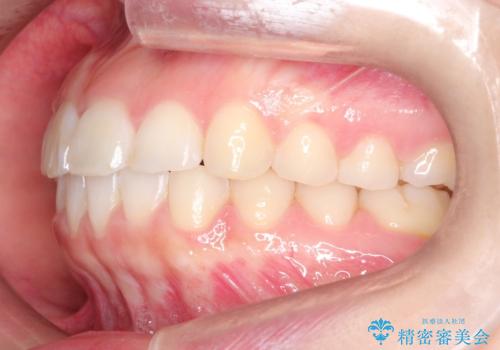

【インビザライン】前歯が出ているのを治したい

- 前歯が出ていることを主訴に来院されました。

前歯の突出感が改善され、満足していただきました。